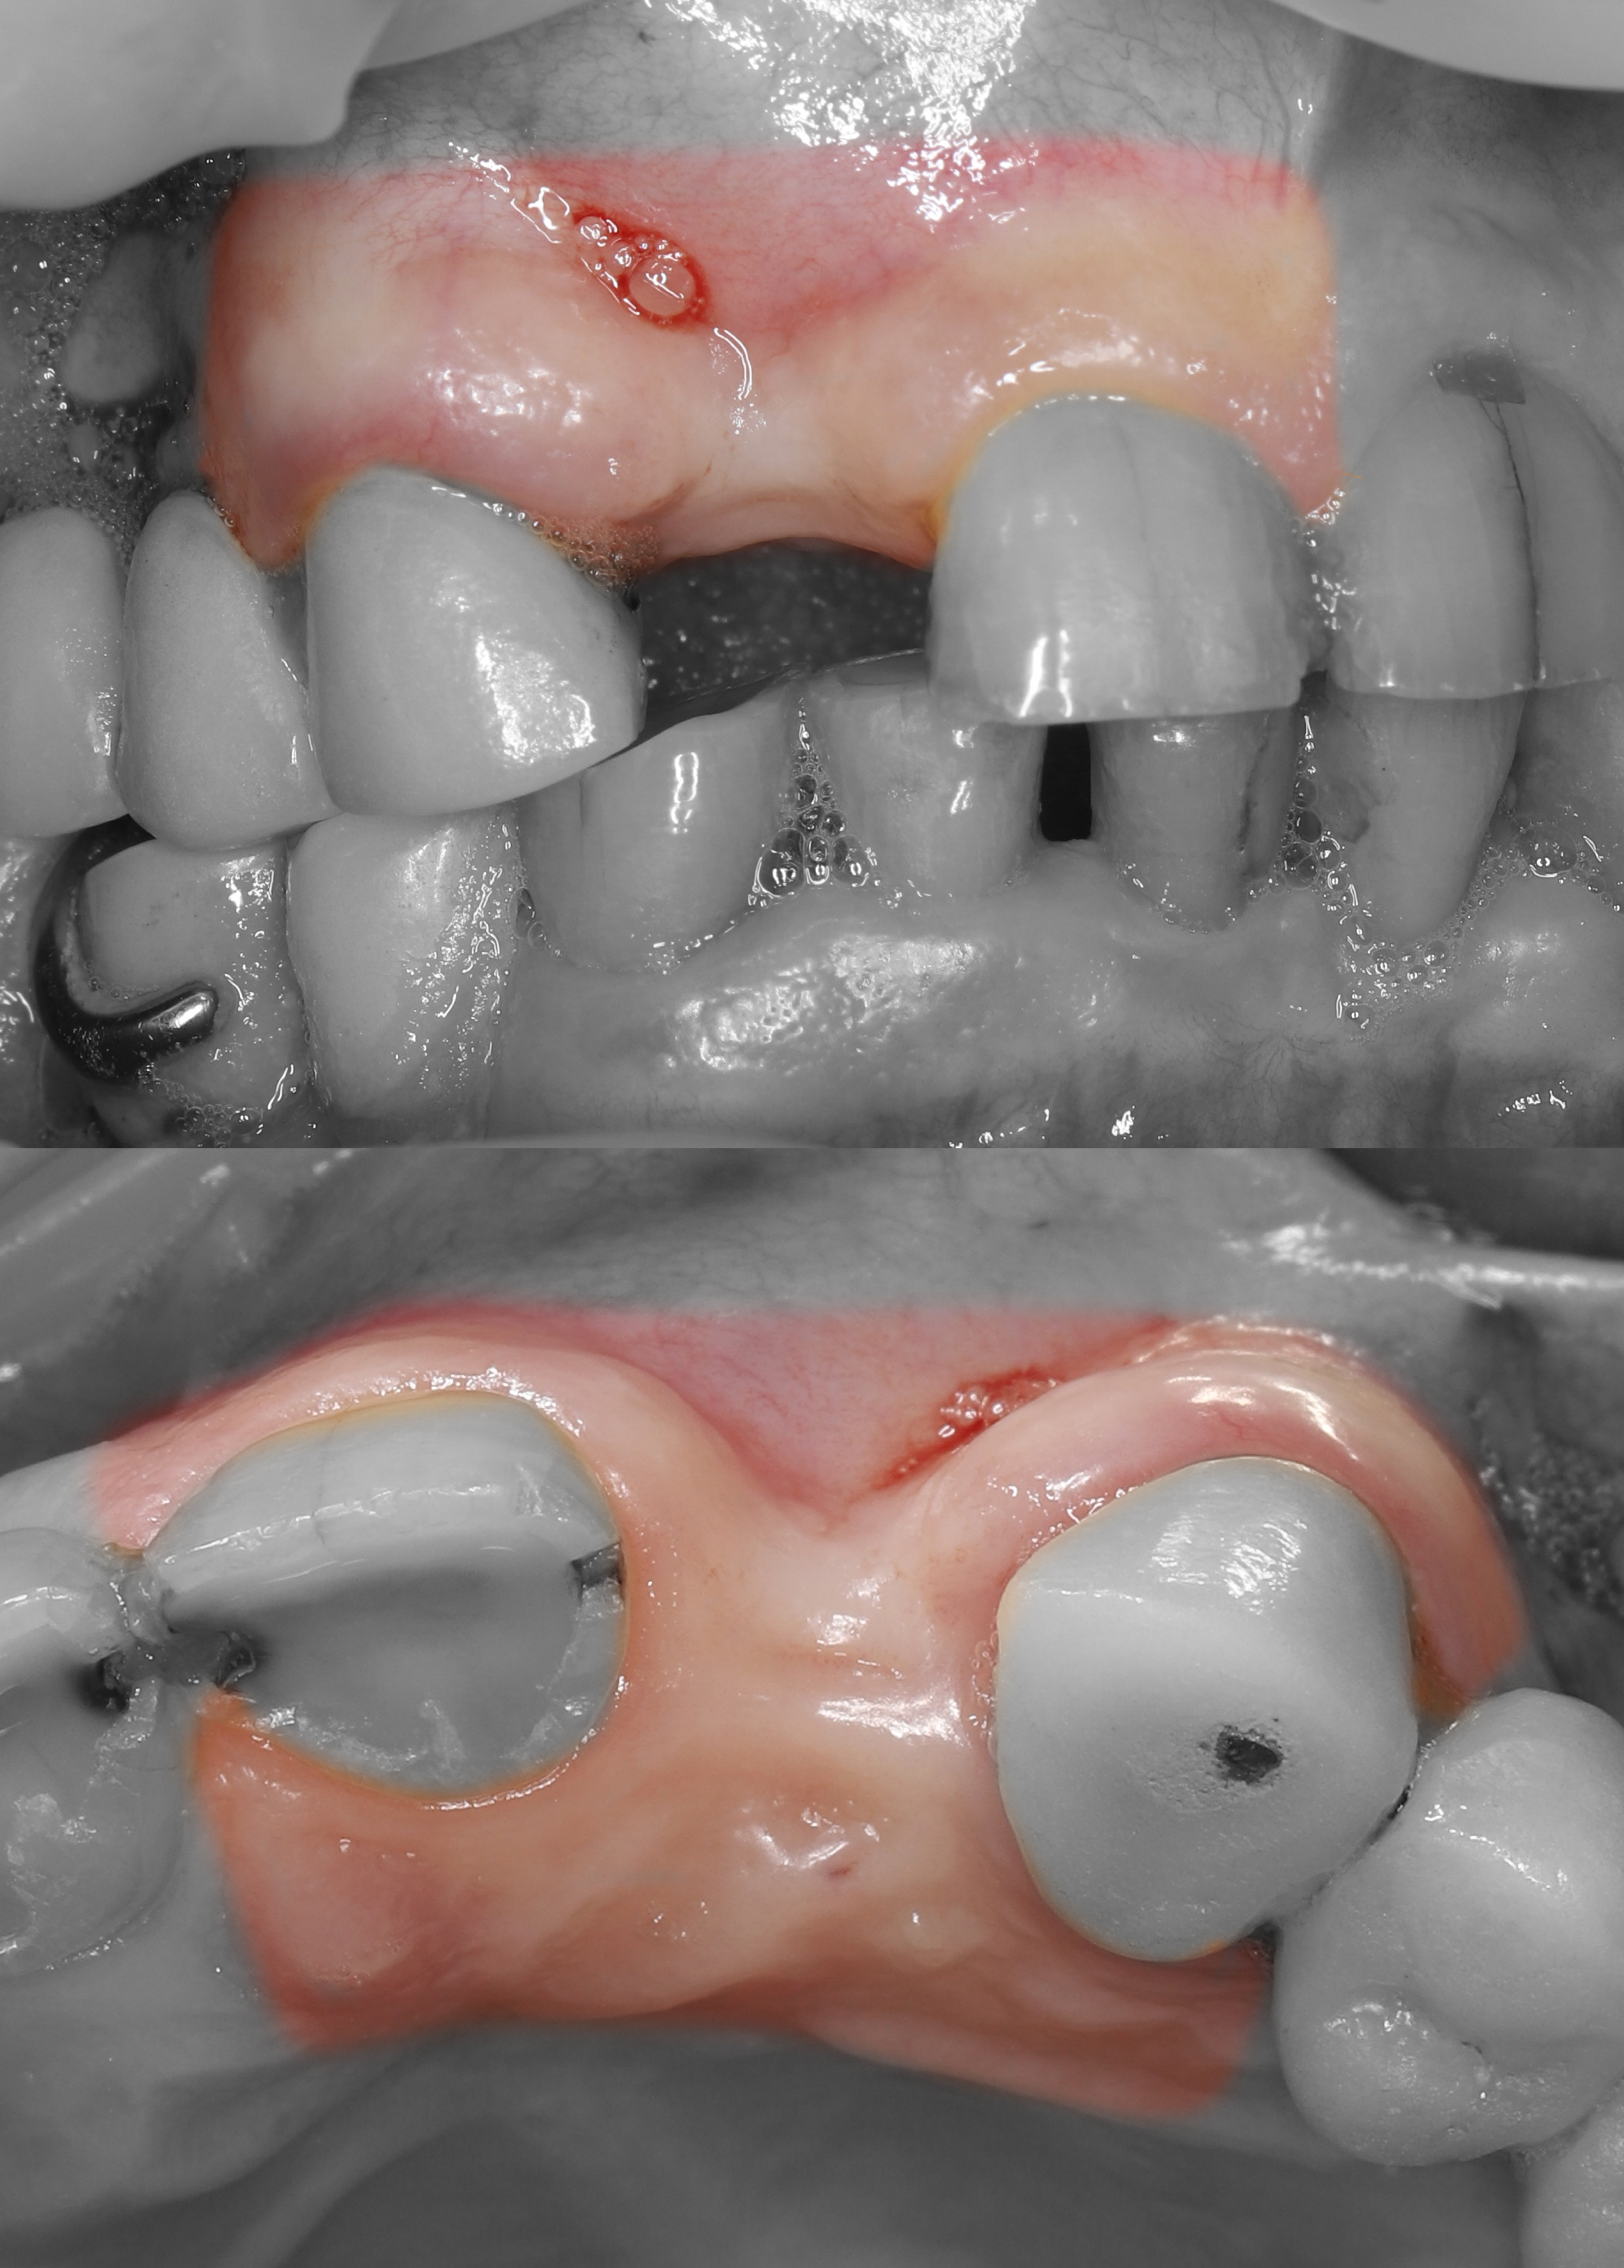

1) Дано: вторичное отсутствие зуба 1.2, выраженный дефект вестибулярных мягких и твердых тканей.

5) Из области бугра ВЧ был получен кортикально-губчатый трансплантат.